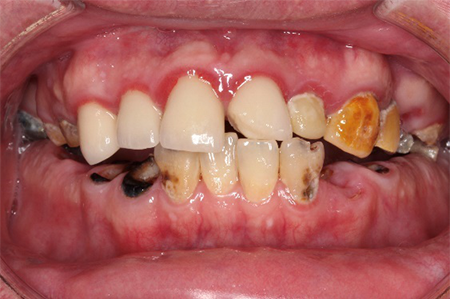

この患者様は長い事歯科医院には通っておらず、下の歯は前歯以外は全て崩壊していることが分かります。

前から見ても歯が欠けてしまい、歯茎も赤く腫れてしまっているのが分かります。

一般的には入れ歯が妥当かと思われますが、患者様は33歳、まだまだ人生は長いです。

奥歯がないと前歯でしか噛めなくなってしまい、残っている前歯もいずれダメになってしまいます。

また、奥歯がなくなってからの期間が長かったため、入れ歯が入るスペースが奥にないのが分かります。

様々なことを鑑み、患者様とも何度も話し合いを行い、下の奥歯には必要最低限のインプラントを、他の歯も外科処置を施しなるべく歯を抜かない方法を取りました。

最終的に抜歯した本数は下の歯5本。上の歯に関しては全て残すことが出来ました。

奥歯があることで前歯の負担を減らし、前歯を失うリスクを下げることが出来ます。